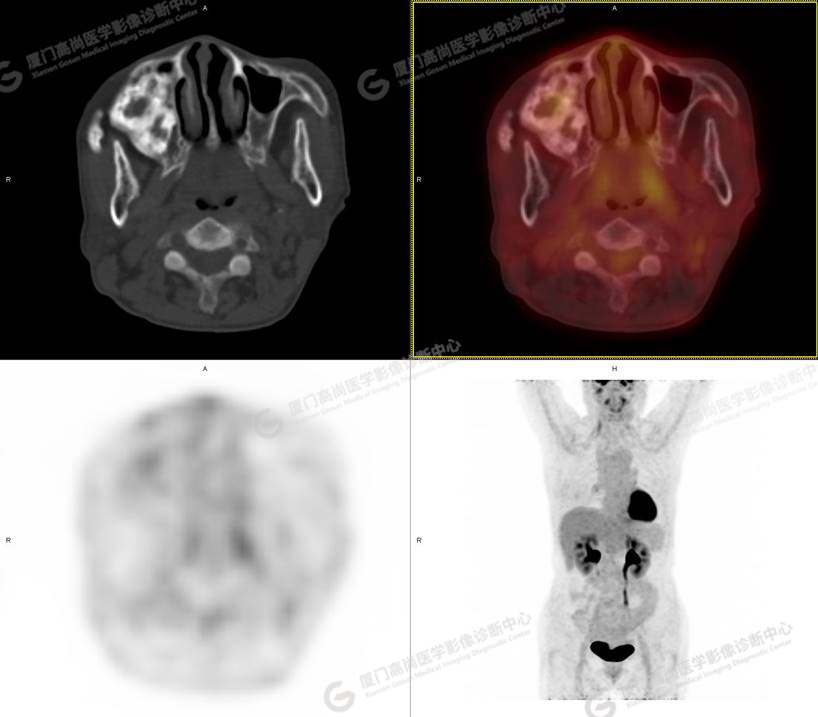

圖1

圖2

PET/CT所見:右側(cè)上頜骨、右側(cè)顴骨及右側(cè)額骨骨質(zhì)膨脹,其內(nèi)密度不均勻性增高,部分放射性攝取輕微增高,SUVmax 2.27。